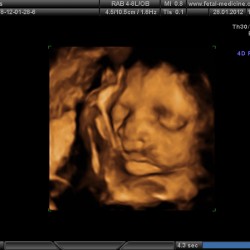

3D and 4D scans provide more detail than the standard 2D ultrasound you’ll have had when the cleft was first diagnosed. They can help parents visualise their baby’s features and may bring comfort or reassurance after receiving a diagnosis.

• 3D scans produce detailed still images.

• 4D scans show moving images of your baby in real time, which may be available as a recording (often at an additional cost).

Images are typically in a warm sepia tone, which helps the sonographer capture clearer pictures.

Please note that 3D/4D scans can sometimes reveal different details or angles compared to standard 2D scans. This might lead to variations in what is seen or discussed. If you have any questions or concerns after your scan, contact your Cleft Team for advice and clarification.